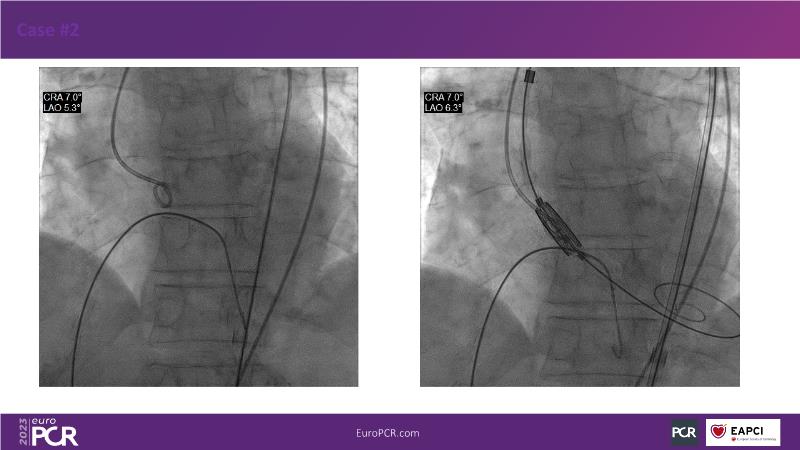

Join this session for an update on the science and clinical advancements in next-generation balloon-expandable transcatheter aortic valve replacement (TAVR) and thin strut bioresorbable scaffolds (BRS). Discover how these innovative technologies can improve clinical outcomes by exploring case-based challenging scenarios and learn effective strategies for tackling them.

- To highlight next generation transcatheter heart valve technologies that can contribute to better clinical outcomes

- To discuss case-based challenging scenarios and how to tackle them